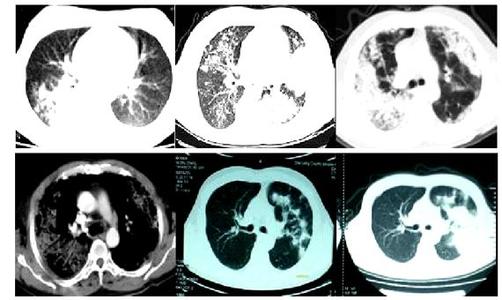

再来说说CT,所谓CT,是Computed TomographyCT的首字母简室,计算机X射线断层扫描技术,是利用X射线束对人体某部一定厚度的层面进行扫描,由探测器接收透过该层面的X射线,转变为可见光后,由光电转换变为电信号,再经模拟/数字转换器转为数字,输入计算机处理成像。该扫描方式是通过单一轴面的射线穿透被测物体,根据被测物体各部分对射线的吸收与透过率不同,由计算机采集透过射线并通过三维重构成像。根据所采用的射线不同可分为:X射线CT(X-CT)以及γ射线CT(γ-CT),一般使用的是X射线CT。CT主要的危害来自于射线源,高能射线源能对人体组织及环境造成不可逆转的破坏,即使是医用的X射线CT,多次的累积使用,X射线依然会对患者被照组织产生一定的影响。CT检查广泛用于胸部腹部盆腔颈部头颅等全身多个部位的扫描检查。